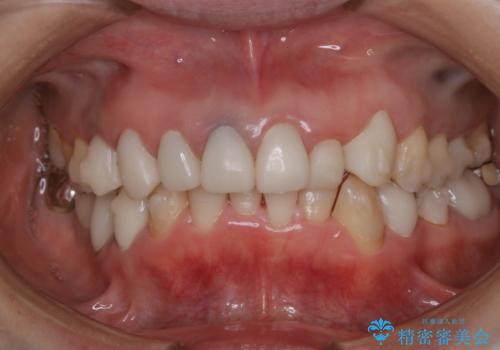

矯正中に患者様で治療と一緒にクリーニング(PMTC30分)

- クリーニングしてほしいとのことで来院されました。

PMTC30分コースを行いました。

矯正の治療日と一緒に行うことで来院回数を減らすこともできるのでおすすめです。

- 歯を白くする目的の施術ではありません